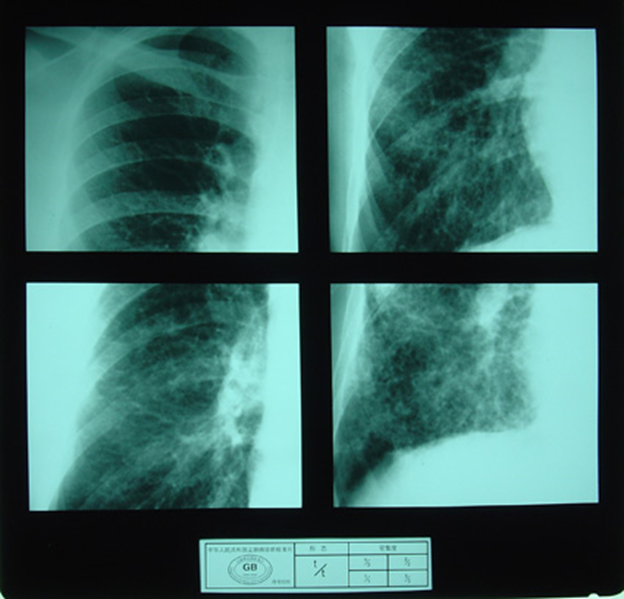

(2)X射线胸片表现:矽肺X射线胸片影像是肺组织矽肺病理形态在X射线胸片的反映,是“形”和“影”的关系,与肺内粉尘蓄积、肺组织纤维化的病变程度有一定相关关系,但由于多种原因的影响,并非完全一致。这种X射线胸片改变表现为X射线通过病变组织和正常组织对X射线吸收率的变化,呈现发“白”的圆形或不规则形小阴影,作为矽肺诊断依据。X射线胸片上其他影像,如肺门变化、肺气肿、肺纹理和胸膜变化,对矽肺诊断也有参考价值。在X射线胸片上,肺野内直径或宽度不超过10mm的阴影。小阴影按其形成分为圆形和不规则形两类。

3)大阴影:在X射线胸片上,肺野内直径或宽度超过10mm的阴影,为晚期矽肺的重要X射线表现,形状有长条形、圆形、椭圆形、或不规则形,病理基础是团块状纤维化。大阴影的发展可由圆形小阴影增多、聚集,或不规则小阴影增粗、靠拢、重叠形成;多在两肺上区出现,逐渐融合成边缘较清楚、密度均匀一致的大阴影,常对称,形态多样,呈八字形等,也有先在一侧出现;大阴影周围一般有肺气肿带的X射线表现。

大阴影

4)胸膜变化:胸膜粘连增厚,先在肺底部出现,可见肋膈角变钝或消失;晚期膈面粗糙,由于肺纤维组织收缩和膈胸膜粘连,呈“天幕状”阴影。

5)肺气肿:多为弥漫性、局限性、灶周性和泡性肺气肿,严重者可见肺大泡。

6)肺门和肺纹理变化:早期肺门阴影扩大,密度增高,边缘模糊不清,有时可见淋巴结增大,包膜下钙质沉着呈蛋壳样钙化,肺纹理增多或增粗变形;晚期肺门上举外移,肺纹理减少或消失。

无尘肺

尘肺壹期

尘肺贰期

尘肺壹期

尘肺贰期

尘肺叁期